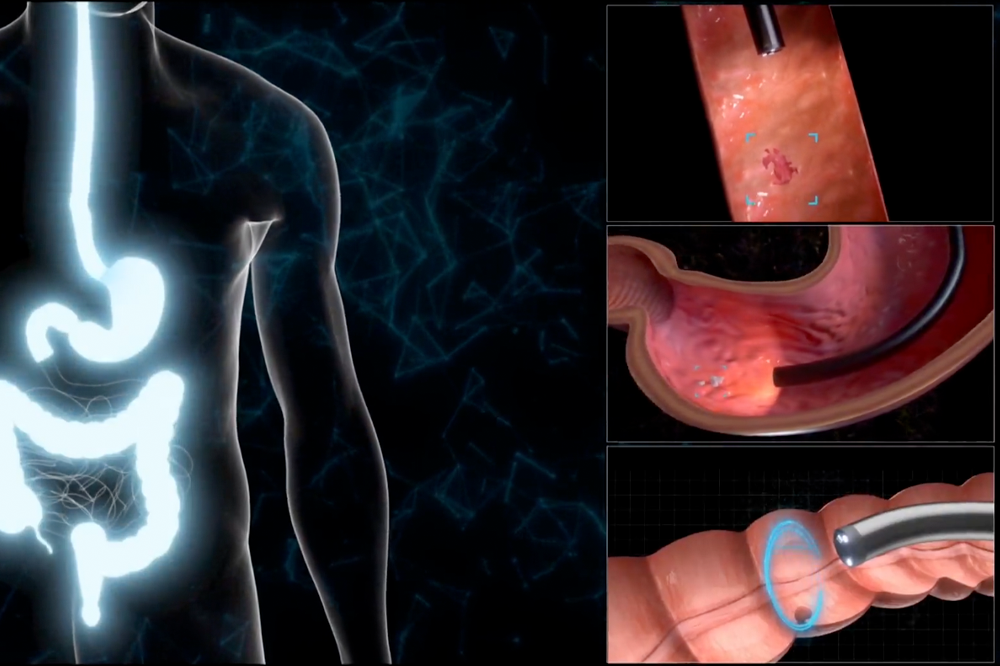

二種類のレーザー光で観察部位を照らし、粘膜表層の血管や微細な異常を強調表示。AI診断支援機能により、検査中に疑わしい病変をリアルタイムで特定し、医師の診断をサポートします。